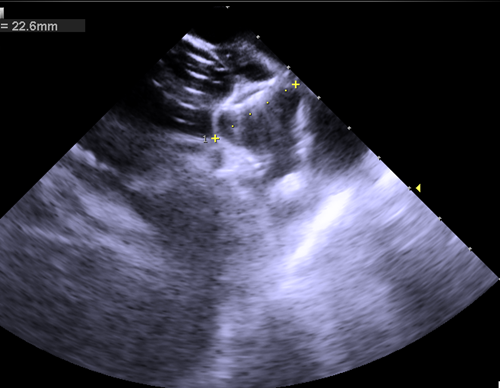

术后三维心腔内超声复查左心耳稳定性

经过术前准备,手术顺利开展,整个手术过程不到2小时,三维心腔内超声在术前对左心耳大小进行测量,术中指导房间隔穿刺,术后评估封堵位置及稳定性,术后李奶奶自述没有任何痛苦,在手术台上睡了一觉就解决了房颤对她带来的困惑,术后恢复已出院。